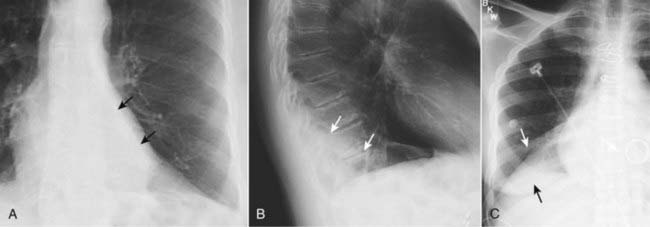

Figure 5-12 Left lower lobe and right lower lobe atelectasis.

A, A fan-shaped area of increased density behind the heart is sharply demarcated by the medially displaced major fissure (solid black arrows) representing the characteristic appearance of left lower lobe atelectasis. B, On the lateral view, the major fissure (solid white arrows) is displaced posteriorly. The small triangular density in the posterior costophrenic sulcus is in the characteristic location for left lower lobe atelectasis on the lateral projection. C, In a different patient there is a fan-shaped triangular density in the right lower lobe bounded superiorly by the major fissure (solid white arrow). Notice how the unaerated lower lobe silhouettes the right hemidiaphragm (solid black arrow).